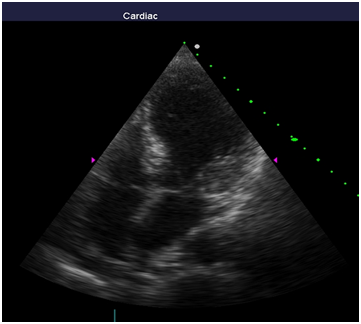

Repeated echocardiography revealed the zone of violation of local contractility (akinesis and pronounced hypokinesis) all segments on the medial and apical level with the formation of acute left ventricular aneurysm, a marked reduction of EF (23%), hyperkinesis all segments at the basal level (Figure 4-8). Troponin test was strongly positive (Figure 9). The patient is re-examined by a cardiologist, on the basis of ECG, Echo pattern, and the presence of markers of myocardial damage diagnosed with acute myocardial infarction in type 2 complicated by development of acute left ventricular aneurysm, acute heart failure Killip class IV. We carried out differential diagnosis between stress cardiomyopathy and myocarditis.

Figure 4 Echocardiography: PLAX, hyperkinesis of the basal segments with apical ballooning.

Figure 5 Echocardiography: 2АС, hyperkinesis of the basal segments with apical ballooning

Figure 6 Echocardiography: 5АС, hyperkinesis of the basal segments with apical ballooning.

Figure 7 Echocardiography: 5АС, hyperkinesis of the basal segments with apical ballooning.

Figure 8 Echocardiography: 4АС, hyperkinesis of the basal segments with apical ballooning.